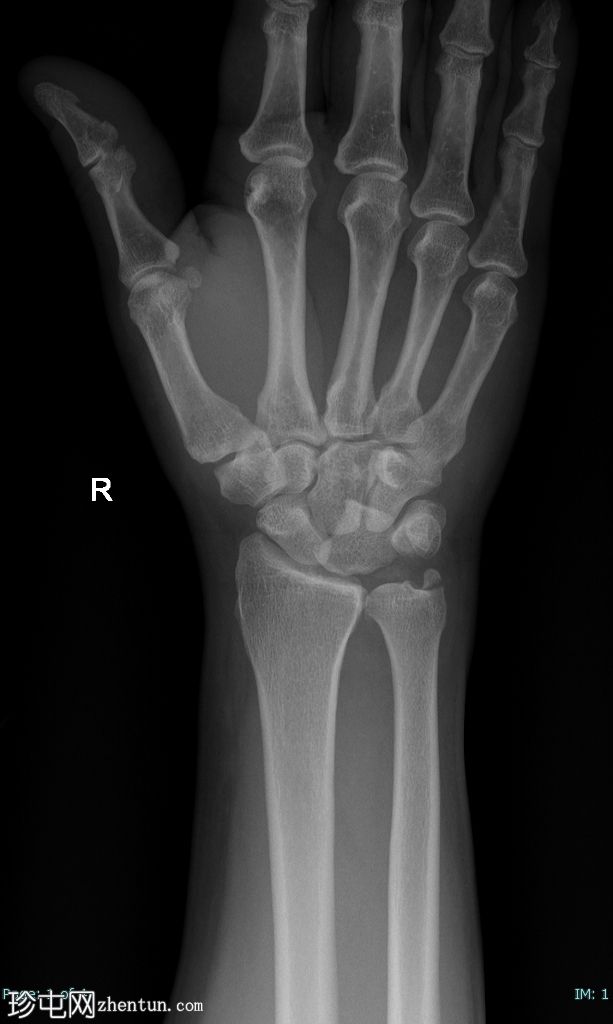

右腕

X线片

正位片

月骨呈“饼状”移位,掌侧成角和移位,侧位片上呈“倾倒的茶杯”样外观。

侧位片上桡骨和头状骨对位正常。

尺骨茎突骨折移位。未见其他骨折。

腕关节处桡骨和尺骨对位正常。

软组织肿胀。